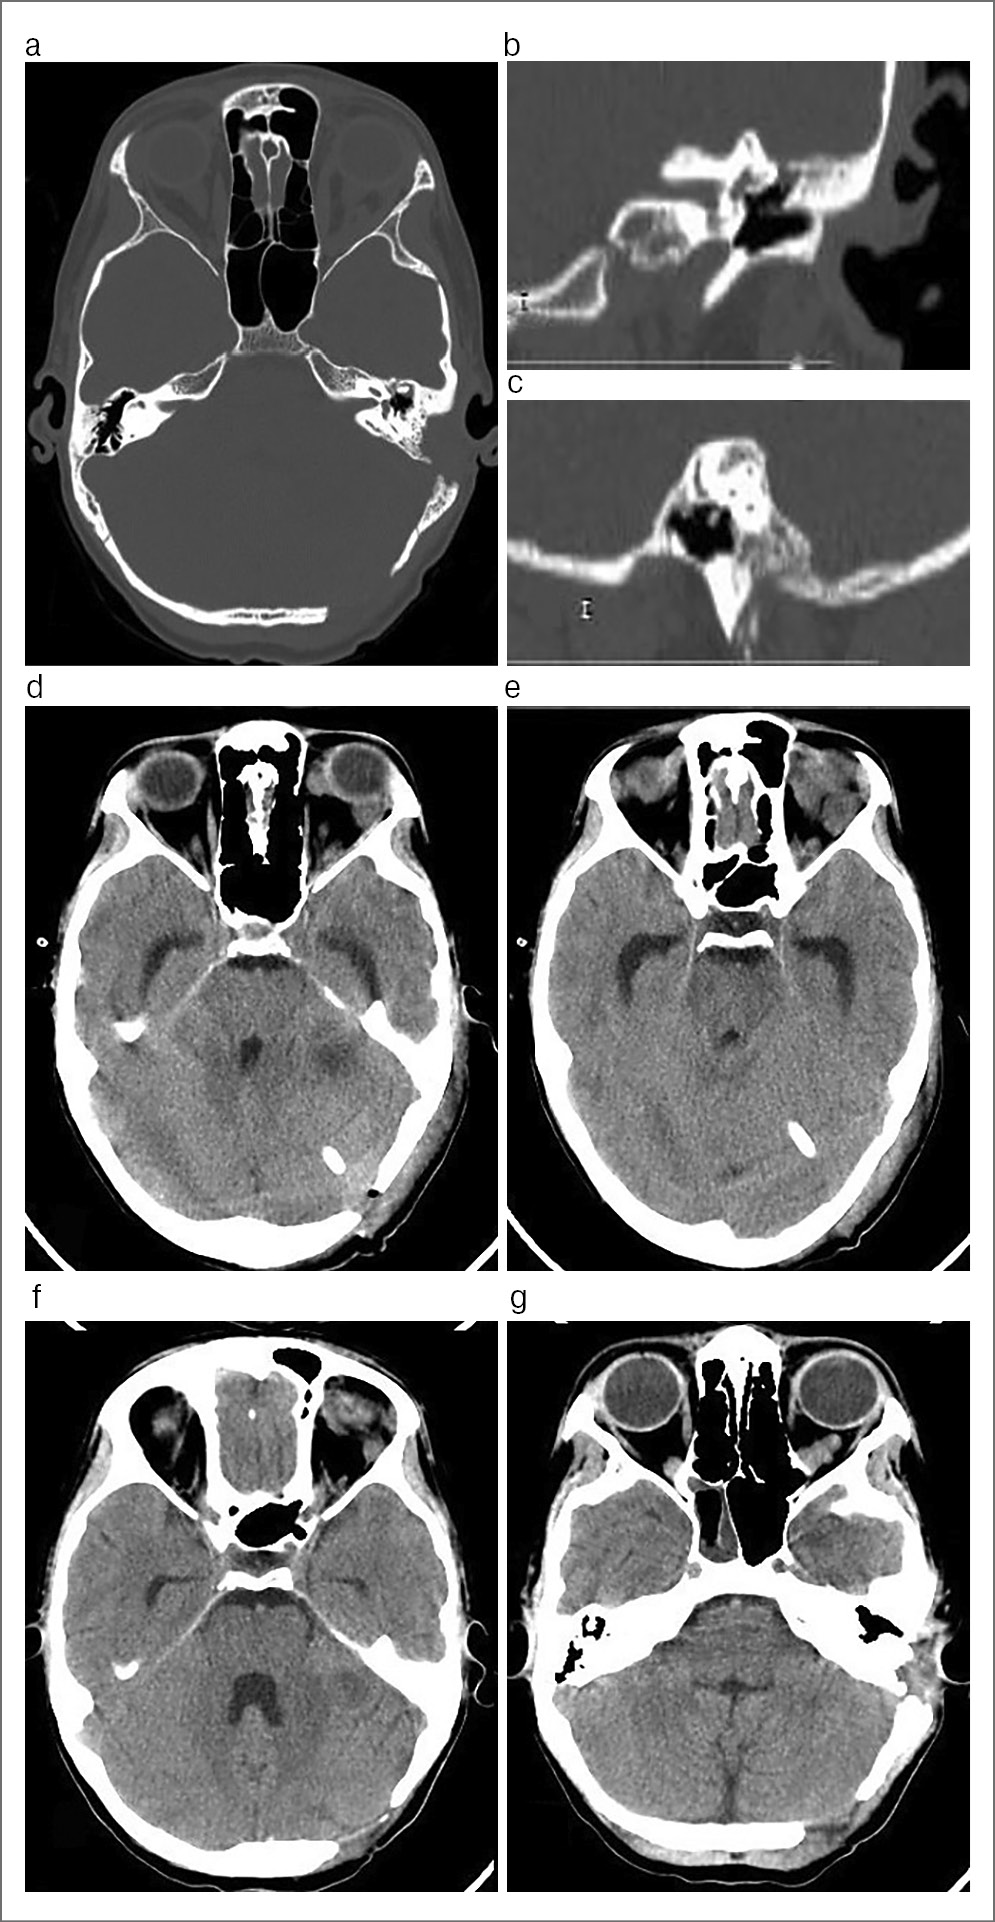

При динамических КТ-исследованиях височных костей, ГМ, выполненных через 5 дней после оперативноголечения, – динамика положительная (рис. 2). Исход лечения – выздоровление.

Рис. 2. КТ височных костей в аксиальной проекции (a), коронарной проекции (b) и сагиттальной проекции (c) и ГМ без контрастирования в аксиальной проекции (d, g) пациента К., 16 лет, выполненные после хирургической санации очагов инфекции. Послеоперационные полости среднего уха и сосцевидного отростка без воспалительных явлений (a, b). На КТ ГМ, выполненных в динамике через 5 дней после оперативного лечения (d, e), жидкостных образований не выявлено, отек вещества ГМ, смещение срединных структур умеренно выраженные. На КТ ГМ, выполненных на 17-е сутки после хирургической санации очагов инфекции (f, g), образований, смещения срединных структур ГМ не выявлено.